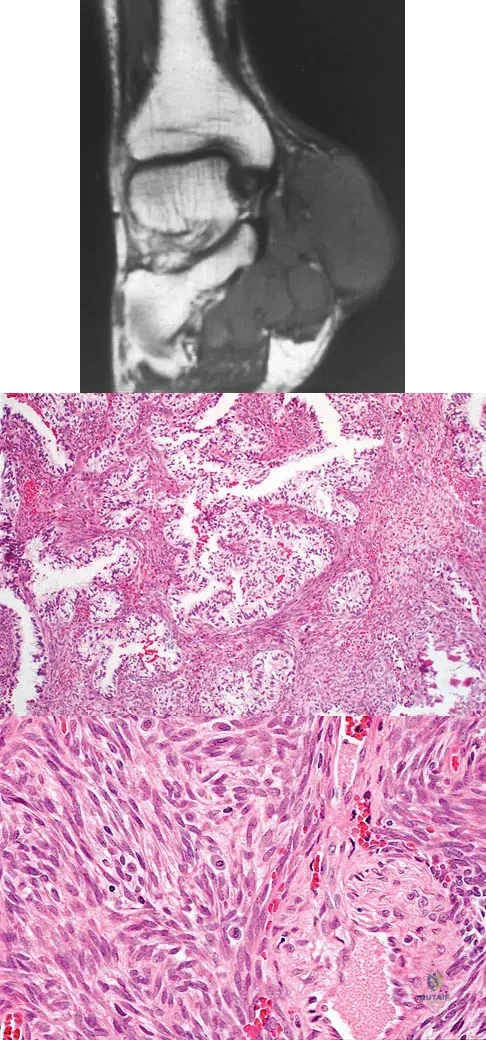

A 40-year-old man has a painless mass around his left ankle. He notes minimal growth over the past year. An MRI scan is shown in Figure 73a, and biopsy specimens are shown in Figures 73b and 73c. What is the most likely diagnosis?

Explanation

The biopsy specimen is a low-power view of a soft-tissue sarcoma with a biphasic pattern of epithelial cells and fibrous spindle cells that are typical of a synovial sarcoma. A deep, painless soft-tissue mass greater than 5 cm in size is suspicious for a sarcoma. The imaging in this patient is indeterminate and the patient requires a biopsy for an accurate diagnosis. The biopsy reveals a tumor with a biphasic appearance consistent with a synovial sarcoma. These tumors are slow growing, occur primarily in the lower extremities, and are found in a younger demographic population compared to malignant fibrous histiocytoma and liposarcoma. They can occur in a biphasic pattern with clumps of epithelial cells and fibrous spindle cells or in a monophasic pattern. Synovial sarcomas stain positively for keratin. Keratin is positive in nearly all biphasic types and in many tumors of the monophasic fibrous type. Sixty percent of these tumors are found in the lower extremity. The area around the knee is the most common location, followed by the ankle and foot. Epithelioid and clear cell sarcomas are found associated with tendon sheaths of the hand and feet and are generally smaller in size. Epithelioid sarcoma may resemble granulomatous inflammation histologically; clear cell sarcoma is composed of nests of clear cells with occasional multinucleated giant cells. Pigmented villonodular synovitis is found within the synovium and is characterized by a villous histologic appearance with hemosiderin-laden macrophages. Malignant fibrous histiocytoma has a storiform histologic pattern with an abundance of pleomorphic cells. Enzinger FM, Weiss SW: Soft Tissue Tumors, ed 3. St Louis, MO, Mosby, 1995, p 757.